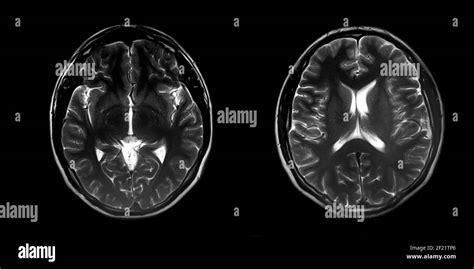

- Neuroimaging: Tecniche come la Tomografia Computerizzata (TC) e la Risonanza Magnetica (RM) cerebrale sono cruciali. Nella demenza vascolare, si possono osservare infarti multipli, lesioni della sostanza bianca, lacune e/o evidenza di patologia cerebrovascolare. Nell'Alzheimer, si osserva tipicamente atrofia cerebrale, più marcata nelle regioni temporali e parietali.